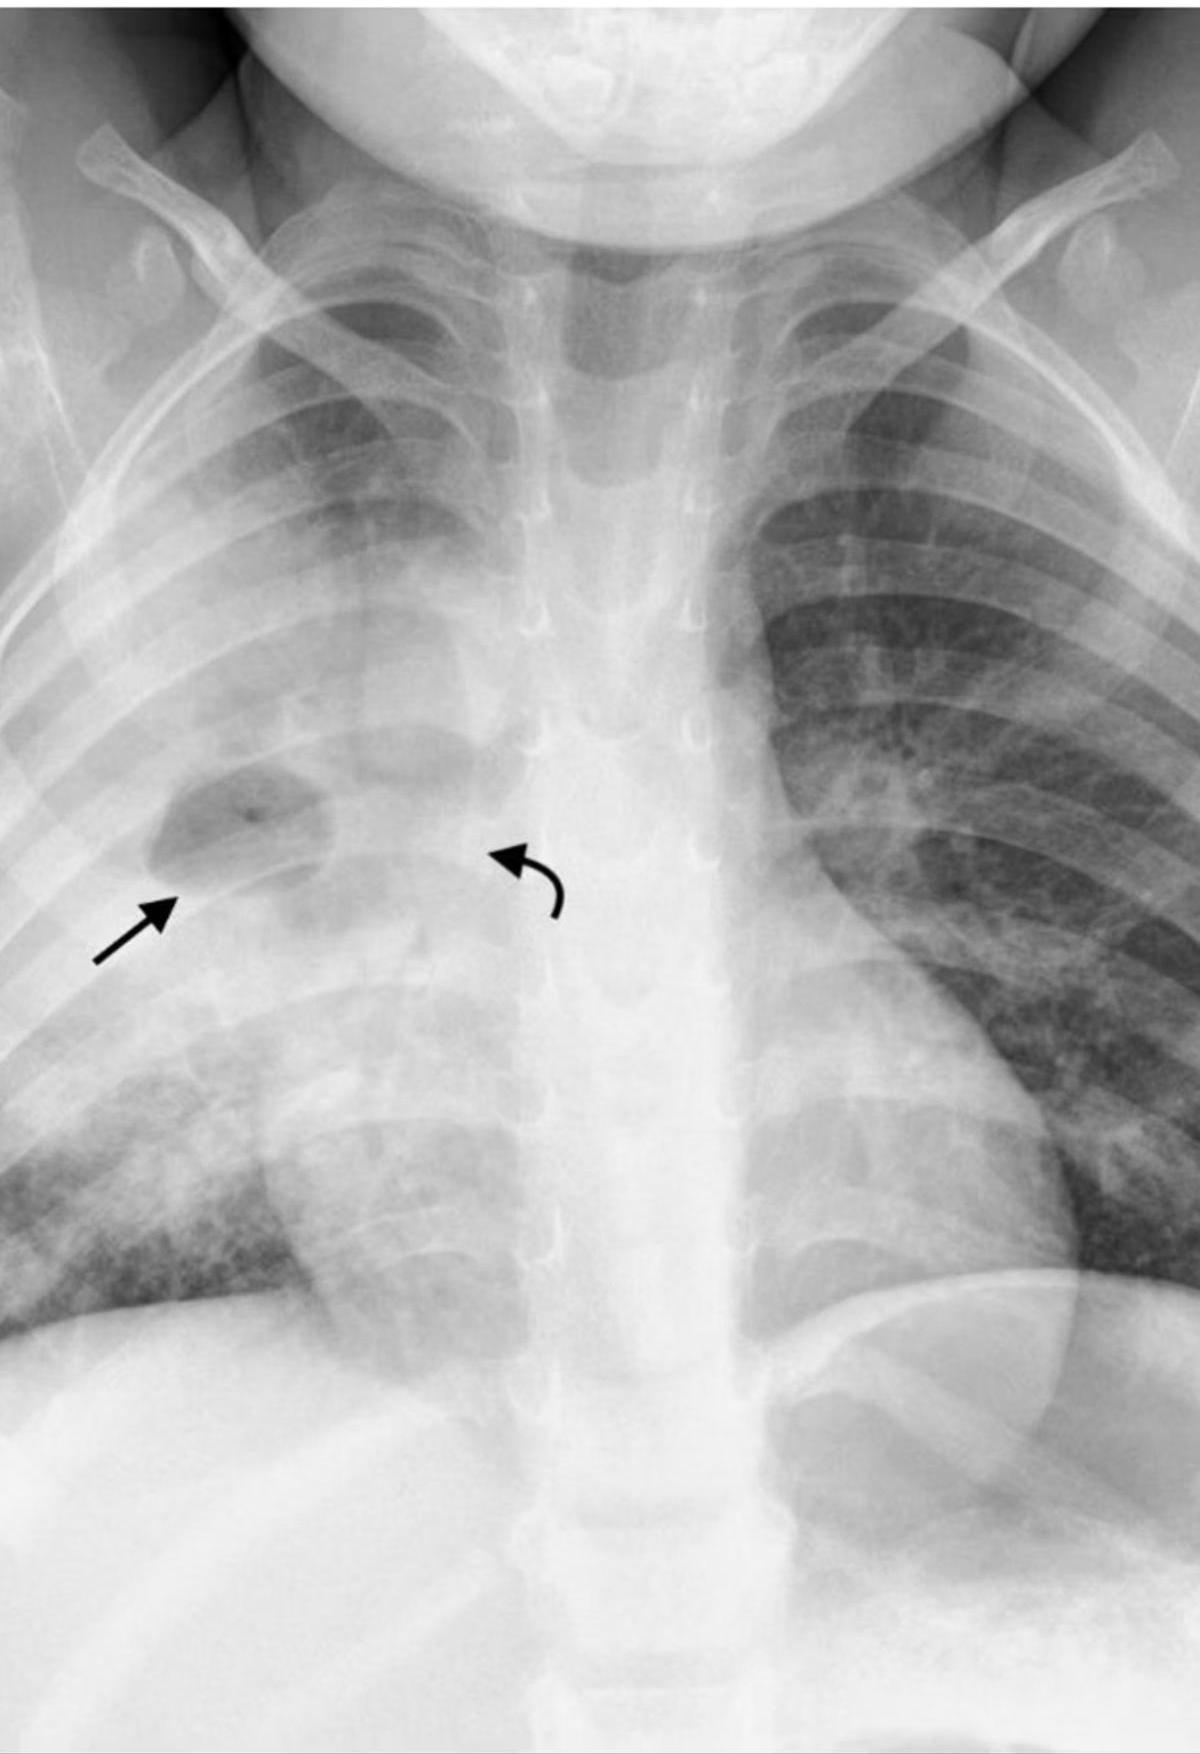

(b) Chest X-ray of pulmonary TB. There is marked left hilar lymphadenopathy.

Pediatric chest x-ray showing hilar lymphadenopathy tuberculosis.

- Hilar/Mediastinal Adenopathy: Most common abnormal finding; often the only visible abnormality in early disease.

Radiography is cornerstone for diagnosis in children due to clinically silent presentations. All lobar segments equally at risk for initial infection. • 25% of cases involve two or more lobes • Hilar lymphadenopathy inevitably present • Partial bronchial obstruction causes air trapping • Progressive destruction leads to cavitation

Diagnostic Imaging Findings Normal Chest X-ray Children with latent TB infection (LTBI) usually have normal-appearing chest radiographs. An isolated calcified lesion with positive TST can be treated as LTBI. Hilar/Mediastinal Adenopathy The most common abnormal radiographic finding in pediatric pulmonary TB. May be the only visible abnormality in early disease. Other Findings Infiltrates, atelectasis, pleural effusions, cavity lesions, or miliary disease pattern may be present in advanced cases.